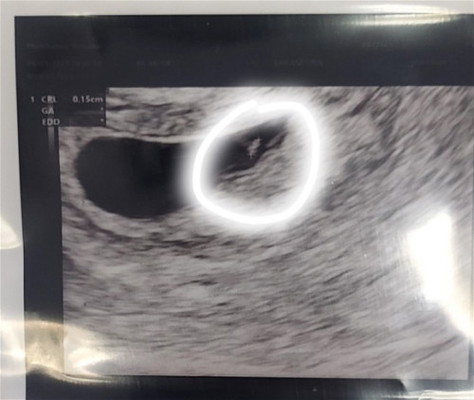

ตรวจตอน6วีค

เราไป ร.พ.เพื่อไปฝากครรภ์แล้วหมอเรย อัลตราซาวนด์ว่ายังไม่เจอตัวน้องค่ะแต่อยากถามว่าที่วงอยู่นั้นเป็นไปได้ไหมค่ะว่าเป็นตัวน้อง..ตัวน้องอาจจะยังจิ๋วอยู่ตอนนี้เครียดมากเรยค่ะกลัวเป็นท้องลม

น้องอาจจะยังจิ๋วอยู่เป็นได้ค่ะส่วนมากจะเจอน้องตอน8wแล้วอย่ากังวลมากค่ะ ส่วนอันที่แม่วงกลมไว้น่าจะเป็นถุงอาหารของน้องหรือเรียกว่าถุงไข่แดงค่ะ